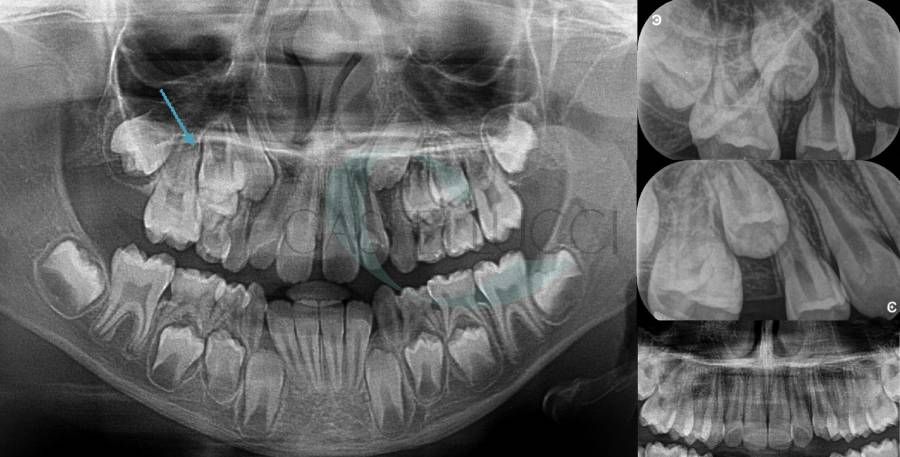

• Diagnosi e terapia delle alterazioni della permuta e delle alterazioni dento-scheletriche legate alle abitudini viziate in dentatura decidua, mista e permanente

• Terapia chirurgica degli elementi dentari decidui con ritardo di permuta

• Disinclusione chirurgica degli elementi dentari permanenti ritenuti